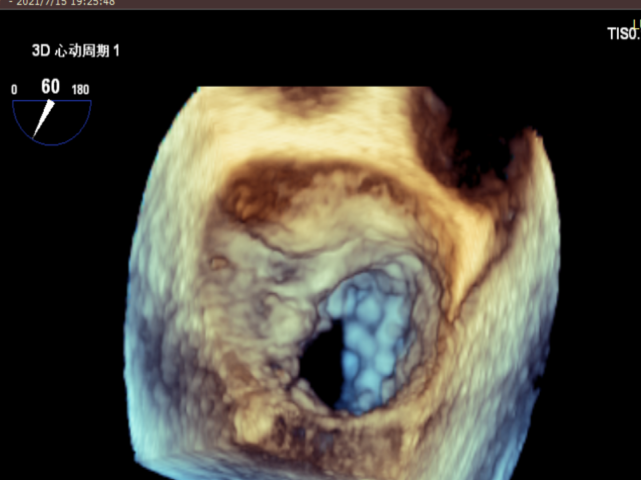

患者全麻后在超声和射线引导下穿刺股静脉-房间隔,器械顺利到达病变的二尖瓣区域,成功完成二尖瓣夹合后,患者二尖瓣反流即刻显著下降,左房压力即刻减低,预示着患者的临床症状将会得到明显改善。